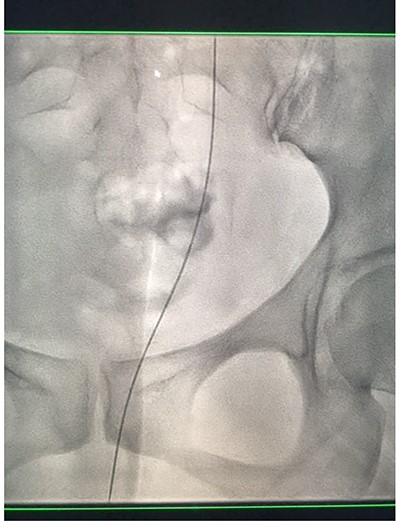

Fluoroscopic images showing the antegrade Amplatz gooseneck snare catheter attempting to grasp the retrograde wire.